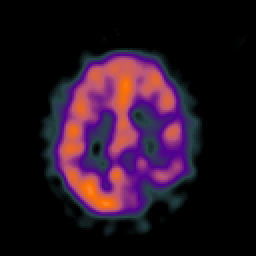

Glioblastoma multiforme overlay -- Slice #37

[Home][Help][Clinical][Tour 1][Tour 2][Tour 3] Slice 37